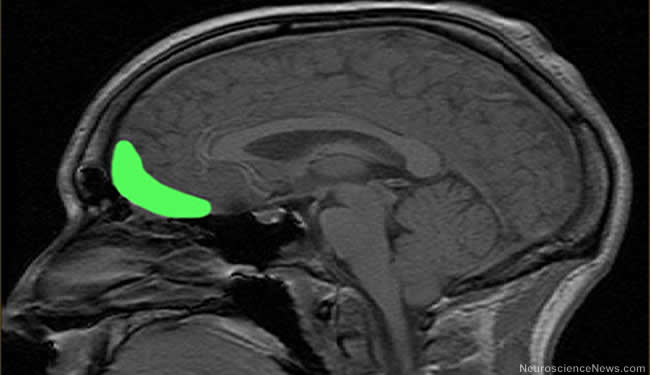

People with psychopathic tendencies have an impaired sense of smell, which points to inefficient processing in the front part of the brain (orbitofrontal cortex) according to a new study.